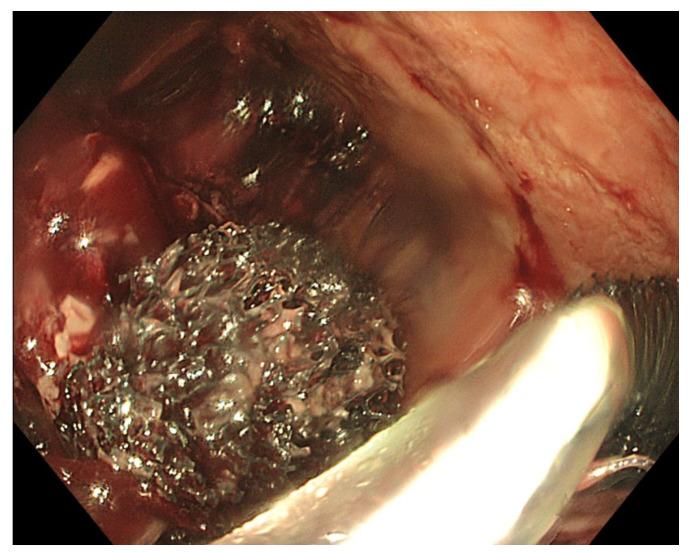

Anastomotic leaks after gastrointestinal surgery have an important impact on surgical outcomes because of the high morbidity and mortality rates. Multiple treatment options exist requiring an individualized patient-tailored treatment plan after multidisciplinary discussion. Endoscopic vacuum therapy (EVT) is a novel treatment option that is nowadays recognized as an effective and useful endoscopic approach to treat leaks or perforations in both the upper and lower gastrointestinal tract. EVT has a very good safety profile. However, it is a time-consuming endeavour requiring engagement from the endoscopist and understanding from the patient. To the unexperienced, the EVT technique may be prone to several hurdles which may deter endoscopists from using it and depriving patients from a potentially life-saving therapeutic option. The current review highlights the possible difficulties of the EVT procedure and aims to provide some practical solutions to facilitate its use in daily clinical practice. Personal tips and tricks are shared to overcome the pre-, intra- and post-procedural hurdles. An instructive video of the procedure helps to illustrate the technique of EVT.

胃肠手术后的吻合口漏由于其高发病率和死亡率,对外科手术结果有重要影响。存在多种治疗选择,需要在多学科讨论后制定个体化的患者定制治疗方案。内镜下真空治疗(EVT)是一种新型治疗选择,如今被认为是治疗上、下消化道漏或穿孔的一种有效且有用的内镜方法。EVT具有非常好的安全性。然而,这是一项耗时的工作,需要内镜医师的参与以及患者的理解。对于没有经验的人来说,EVT技术可能容易遇到几个障碍,这可能会阻碍内镜医师使用它,使患者失去一种可能挽救生命的治疗选择。本综述强调了EVT操作可能存在的困难,旨在提供一些实用的解决方案,以促进其在日常临床实践中的应用。分享了个人的技巧和窍门,以克服术前、术中和术后的障碍。一段该操作的指导性视频有助于说明EVT技术。